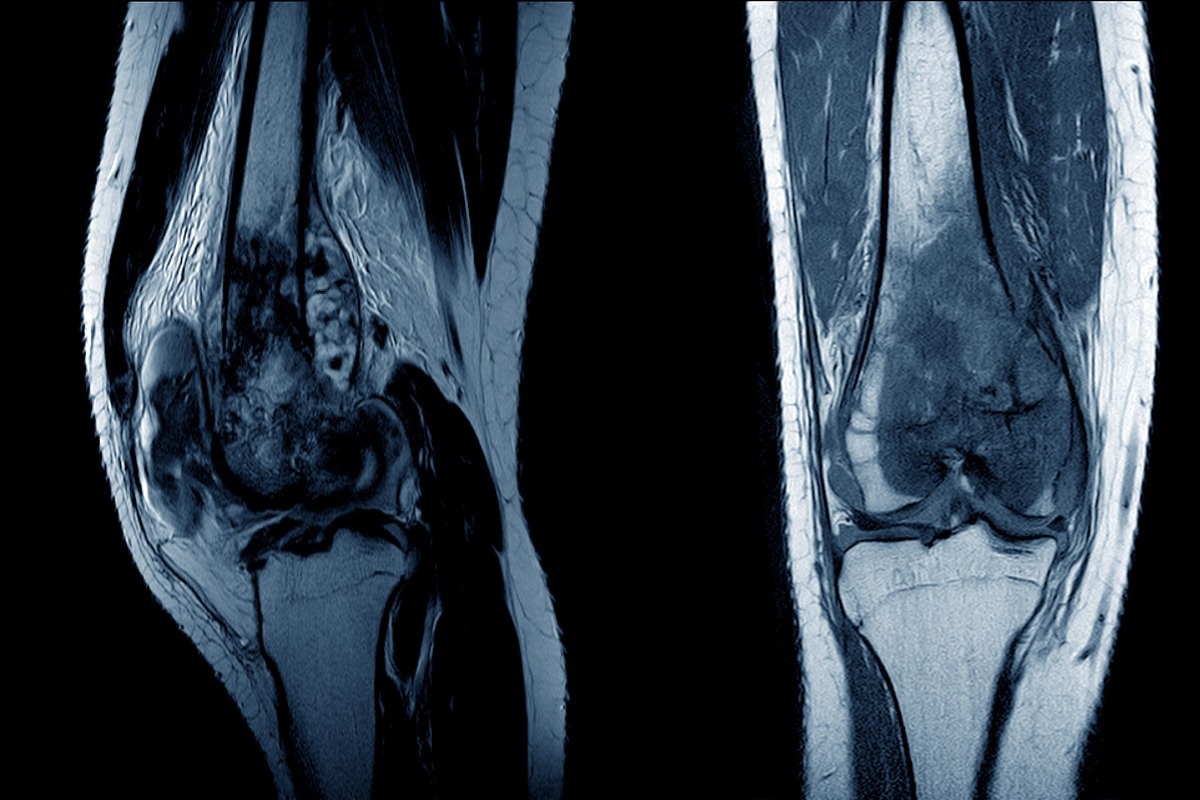

Image Credit: April stock/Shutterstock.com